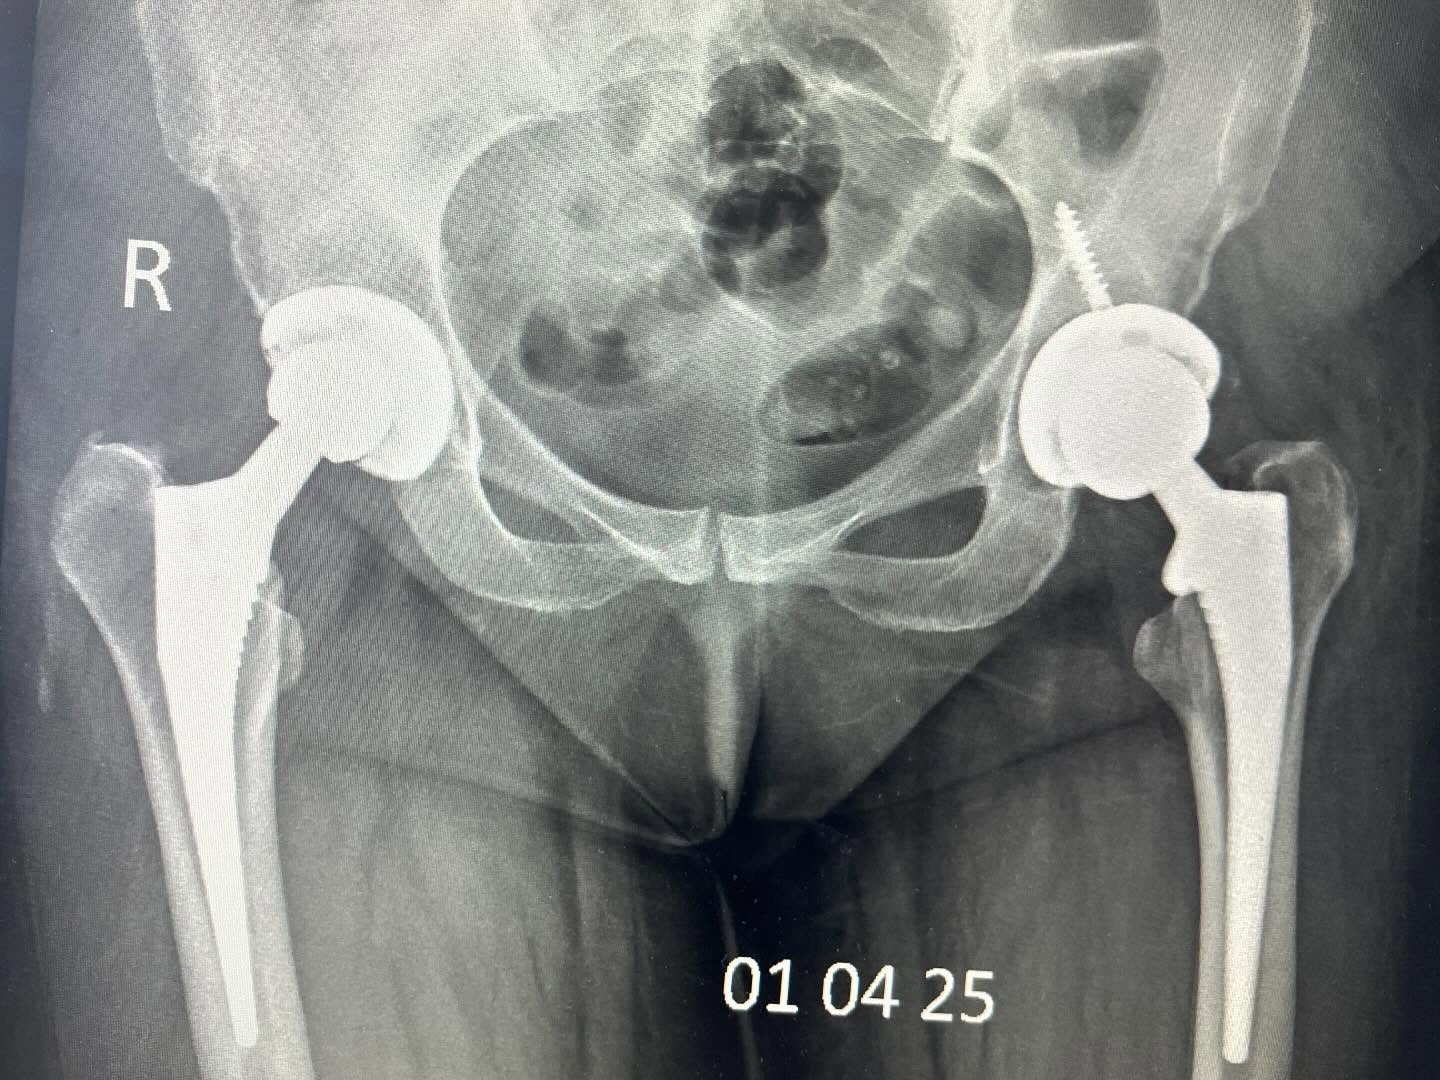

Для порівняння, наскільки змінилися тенденції в практиці ендопротезування. На обидвох фотографіях – одна жінка в різний час після оперування. Справа – це 7 років тому. Зліва – нещодавно проведена операція. Як бачимо, сьогодні все частіше використовуються компоненти більшого діаметра (тобто не 28 мм., як 7 років тому, а 32 мм. та 36 мм. діаметр голівки), які демонструють кращі експлуатаційні характеристики та довший строк служби.